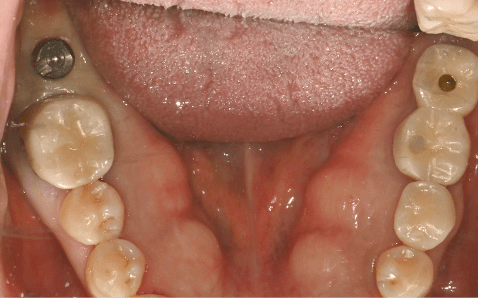

Case 01

Before Implant Placement Right After Flapless Implant Placement

Photo Date : 2024.12.05